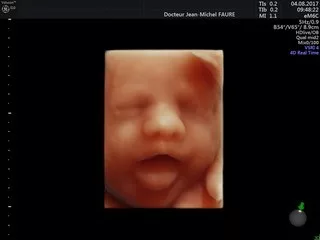

Jean-Michel FAURE

Dr Faure